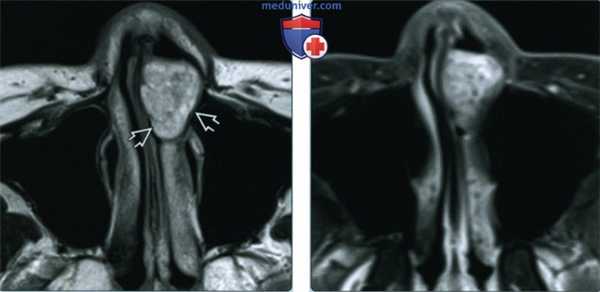

(Слева) При аксиальной МРТ Т2 в передних отделах полости носа слева определяется хорошо отграниченная, неоднородная, гиперинтенсивная доброкачественная смешанная опухоль (ДСО), происходящая из передних отделов носовой перегородки.

(Справа) При аксиальной МРТ Т1 С+ FS в передних отделах полости носа определяется ДСО, активно накапливающая контраст. Центральное контрастное усиление позволяет исключить полип носа, но лучевые признаки неспецифичны; в дифференциально-диагностический ряд необходимо включать иные неопластические процессы.